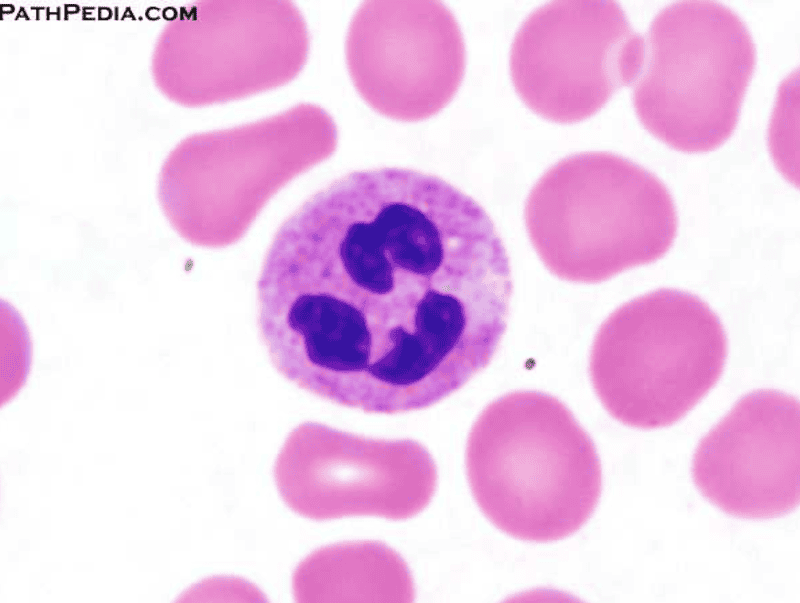

Neutrophil

[Function of a] Neutrophil

Phagocytize pathogens or debris

Order of Leukocytes from most numerous to least numerous

Neutrophil --> Lymphocyte --> Monocyte --> Eosinophil --> Basophil

(Never Let Monkeys Eat Bananas)